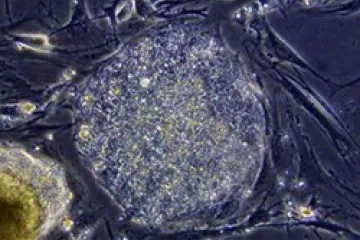

Células fetais são menos imunogênicas, o que significa que são mais fáceis de transplantar, mas Kuebler disse que outras células-tronco não imunogênicas estão disponíveis.

Mas existem alternativas éticas, como células-tronco pluripotentes, tecnologia CRISPR e células-tronco adultas.

“Com nossa capacidade de usar e manipular células-tronco adultas e células-tronco pluripotentes induzidas por humanos, a necessidade de tecido fetal para pesquisa está se tornando obsoleta. Nossa capacidade de desenvolver organoides a partir de tecido adulto também está tornando isso obsoleto”, disse o biólogo.